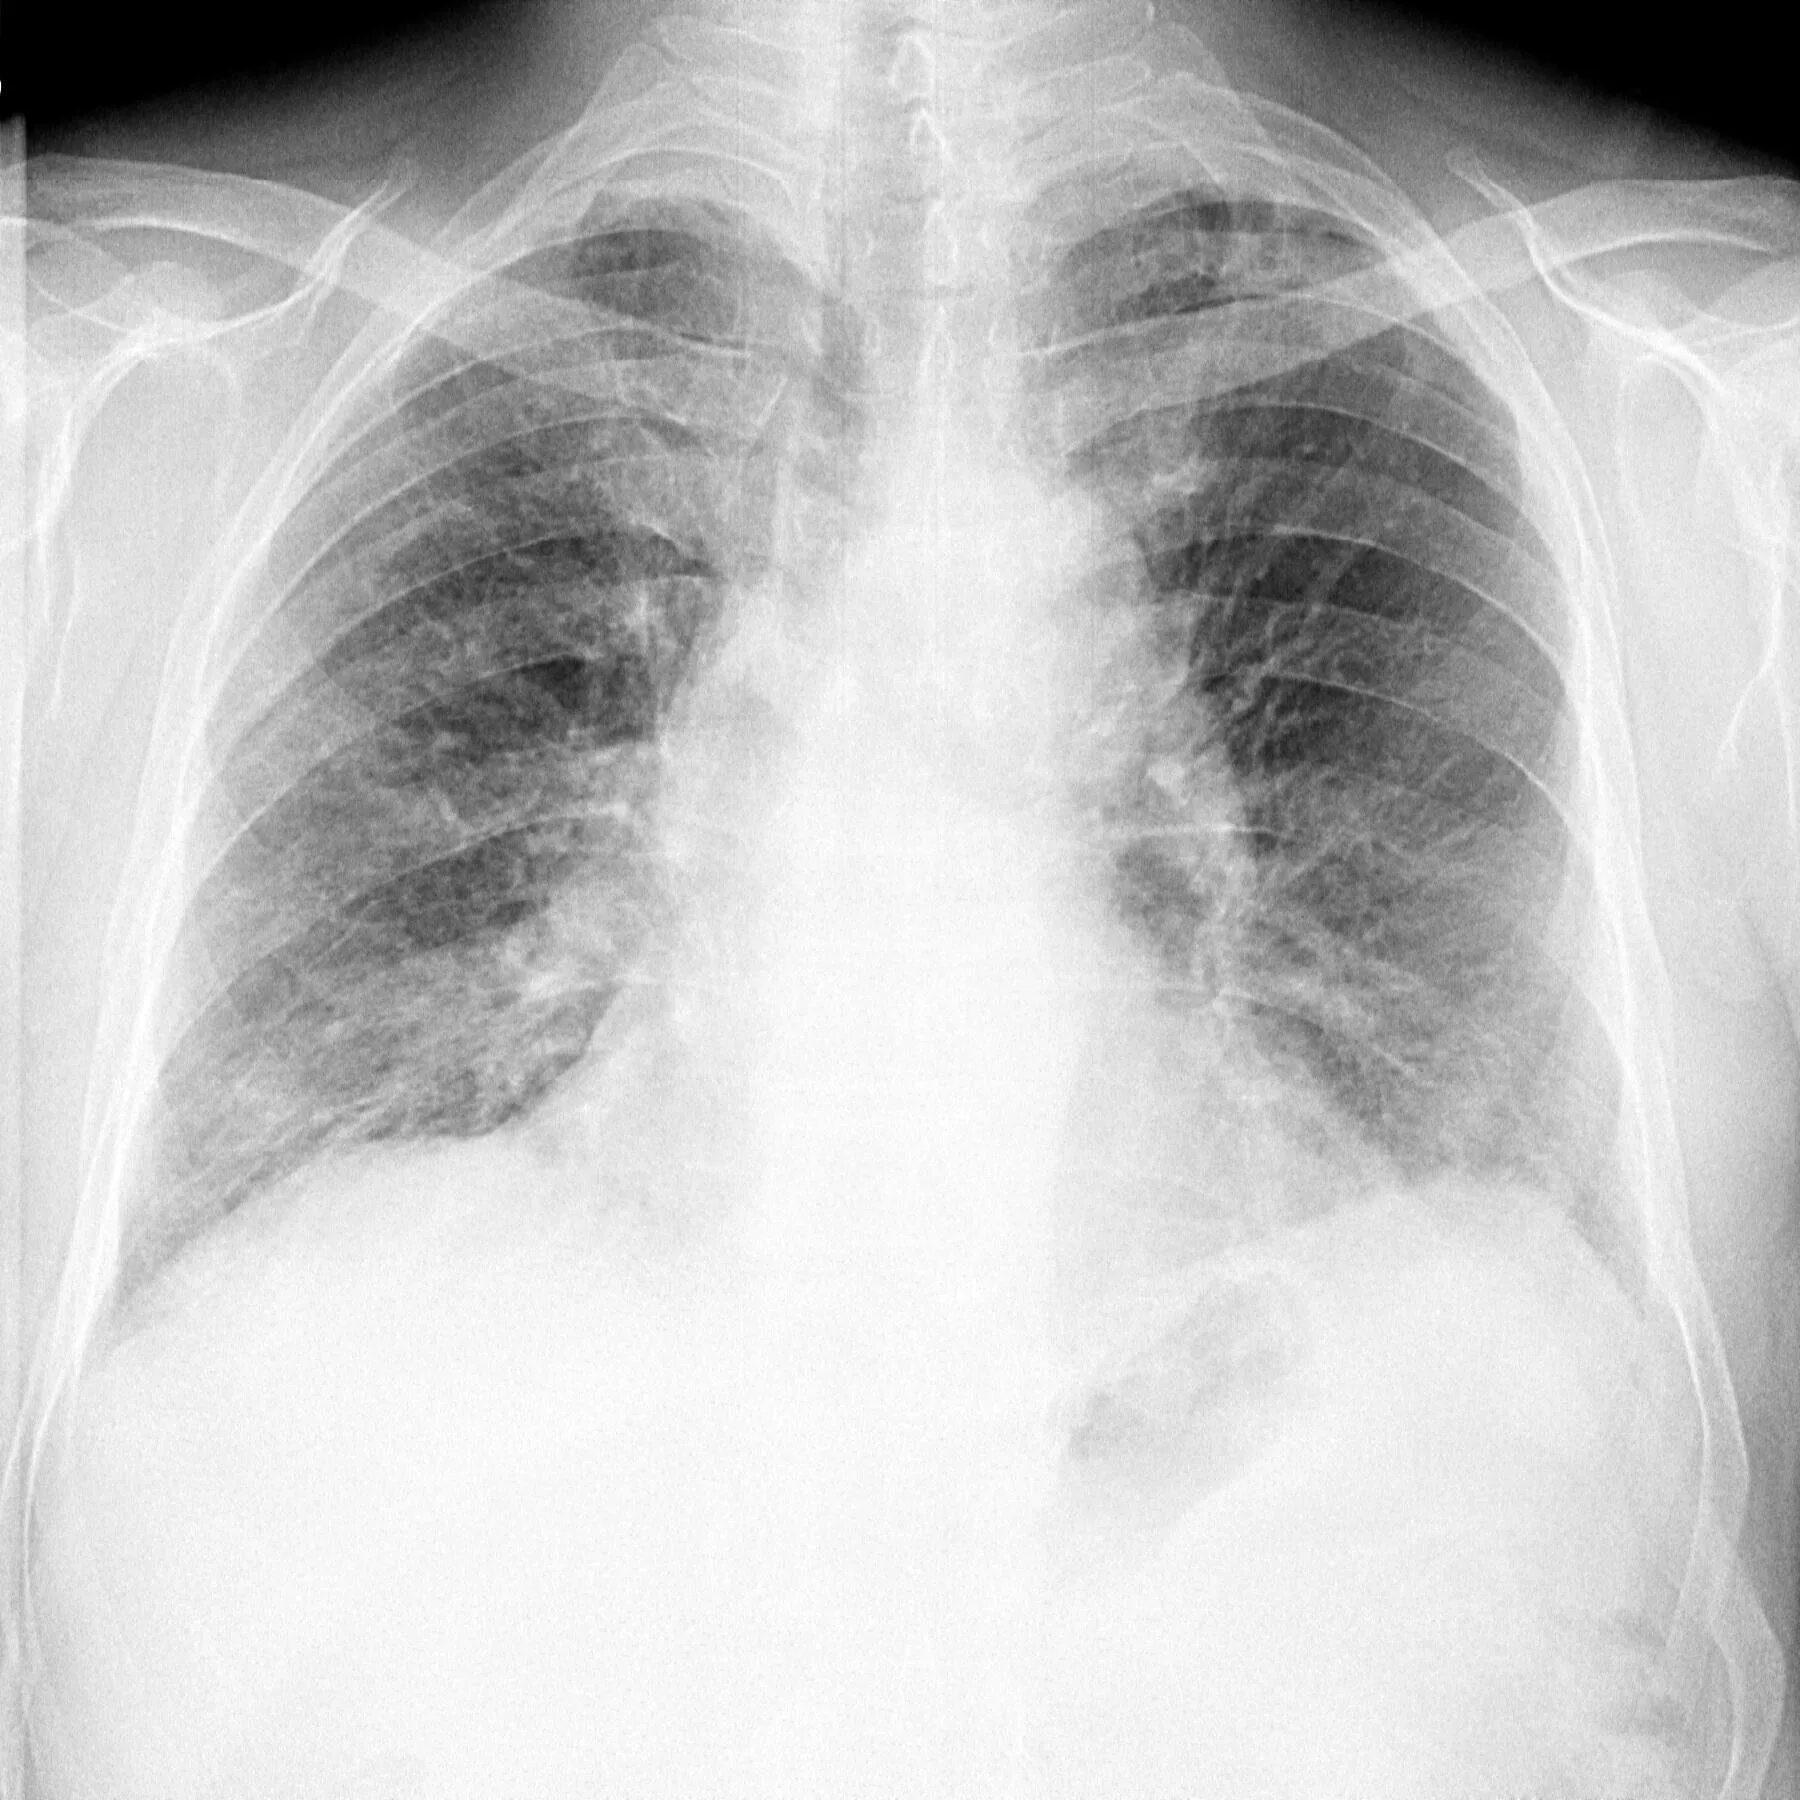

Дыхательная при пневмосклерозе